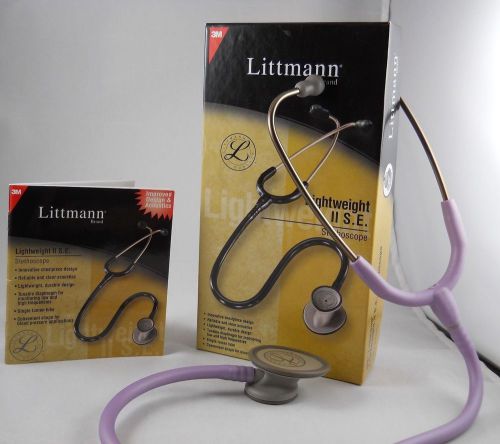

Littmann Lightweight II SE Stethoscope by 3M